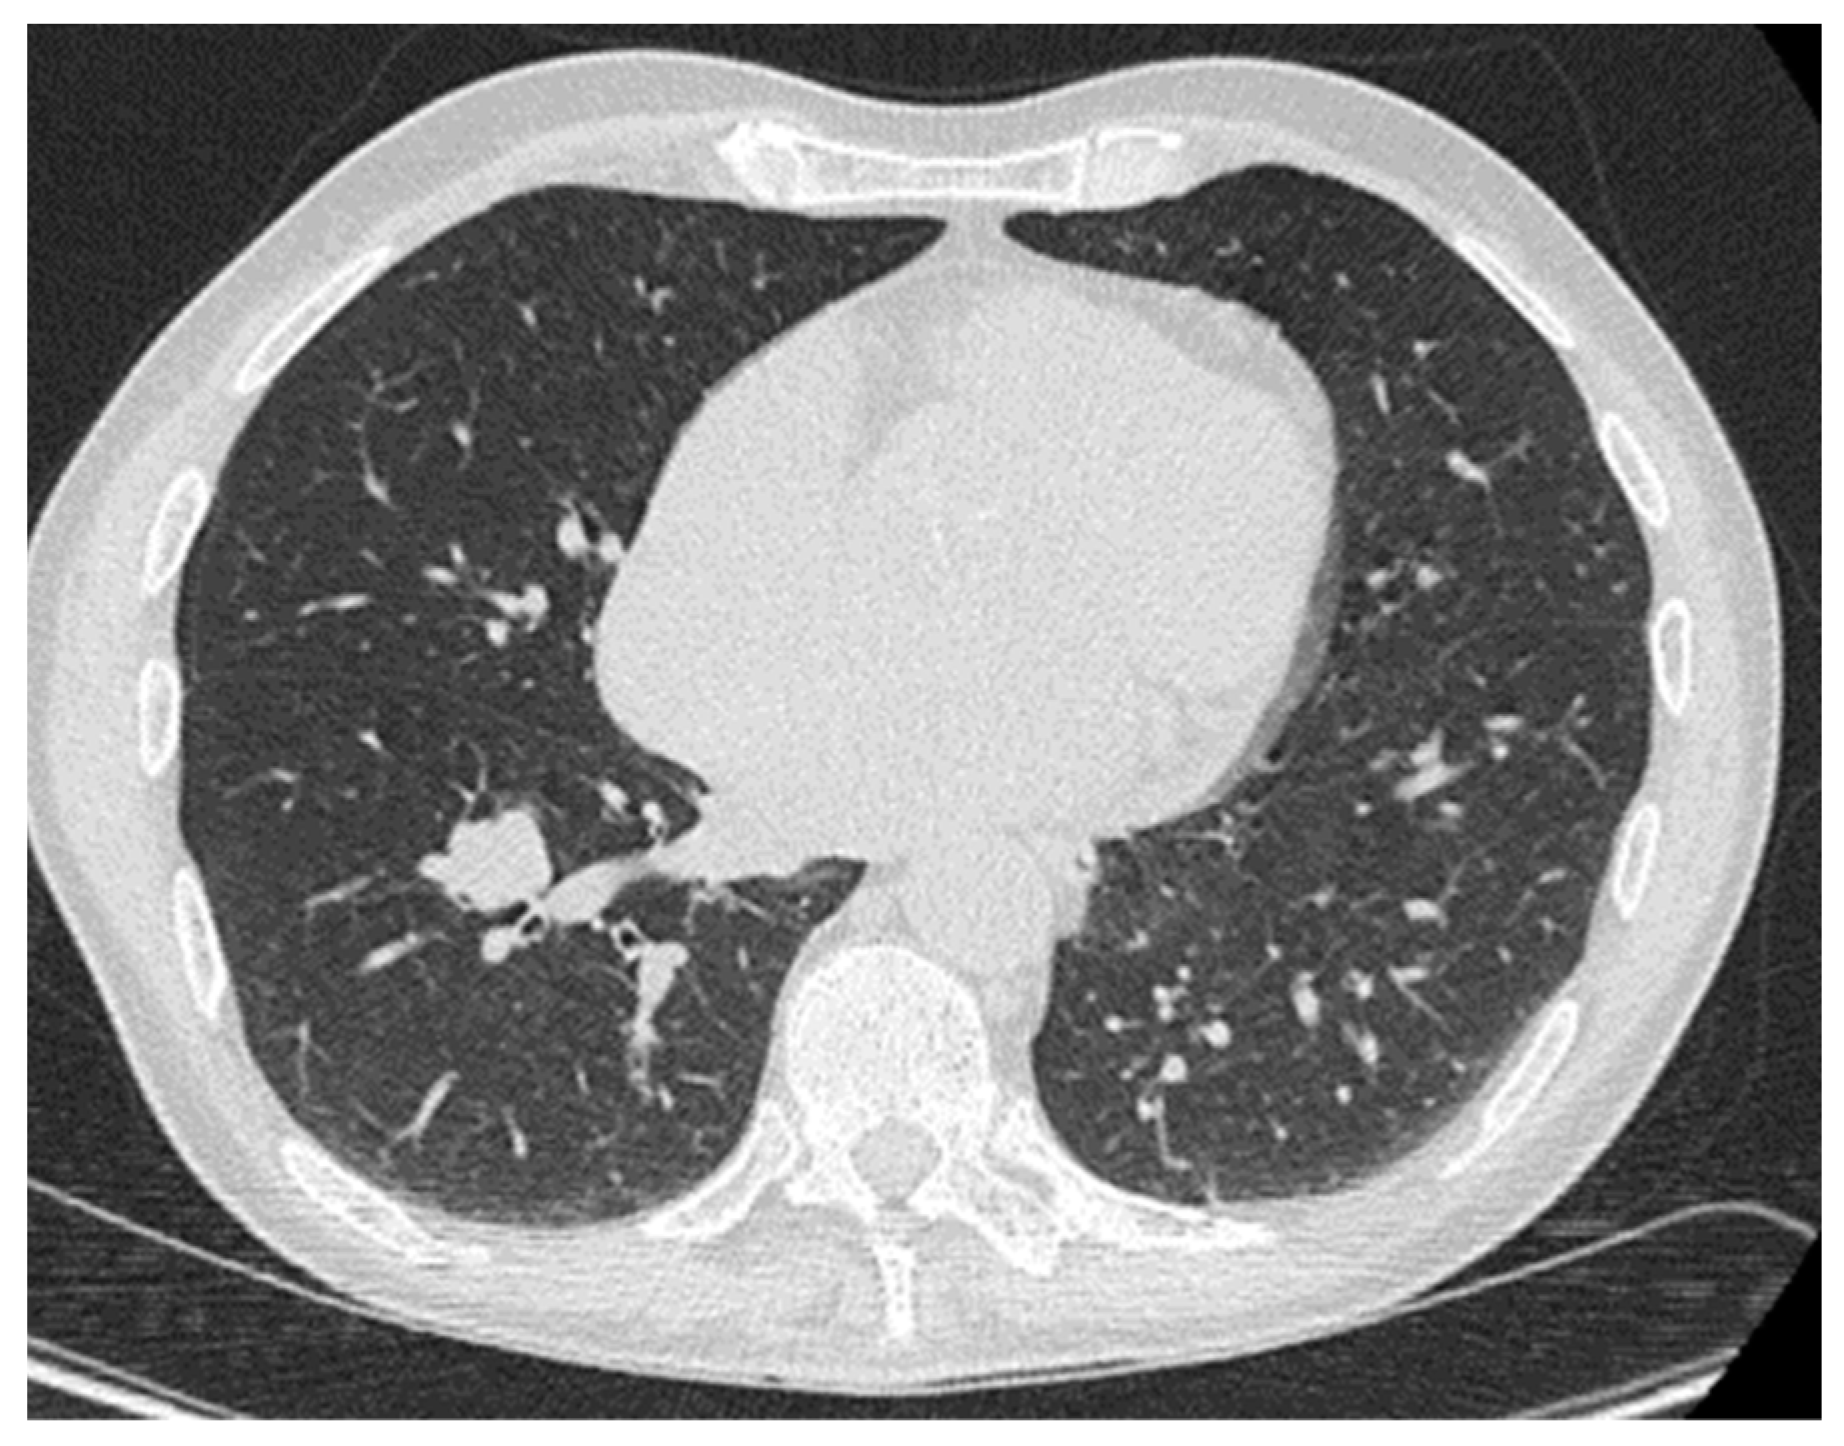

2. Lung